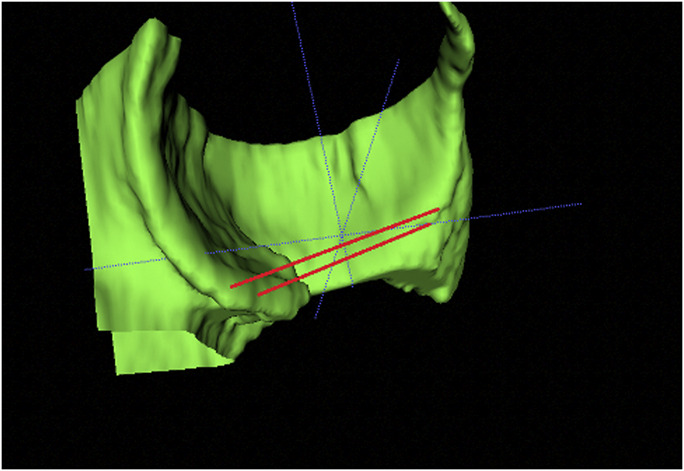

Methods: A prospective database was queried to identify patients with adverse (n = 70) spinopelvic characteristics. These were matched for age and sex with patients without adverse characteristics (n = 70). Spinopelvic characteristics were obtained from radiographs and computed tomography (CT) scans. CT scans were segmented to determine native acetabular anatomy, particularly anteversion. Three hip-spine planning algorithms were evaluated for each patient (Optimized Positioning System [OPS], Combined-Sagittal Index [CSI], Hip-Spine Classification). Differences between target orientations and native anatomy were determined. Agreement between algorithms was tested.